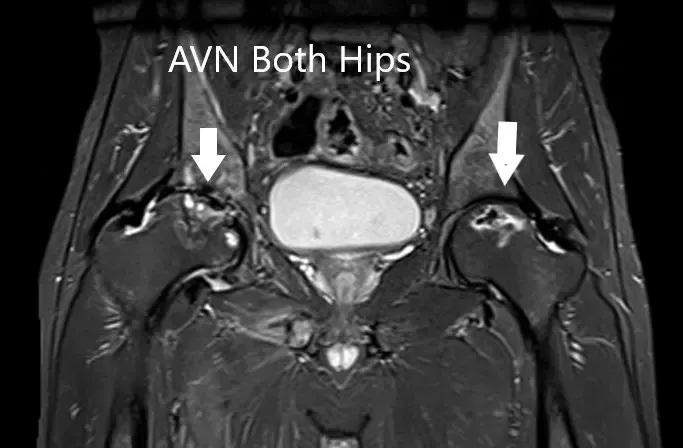

La resonancia magnética sugirió una marcada atenuación de señales en las cabezas femorales bilaterales. Hubo un colapso de la cabeza derecha y un precolapso en la etapa 2a de la cadera izquierda.

Resonancia magnética que muestra AVN bilateral de la cabeza femoral en T1WI